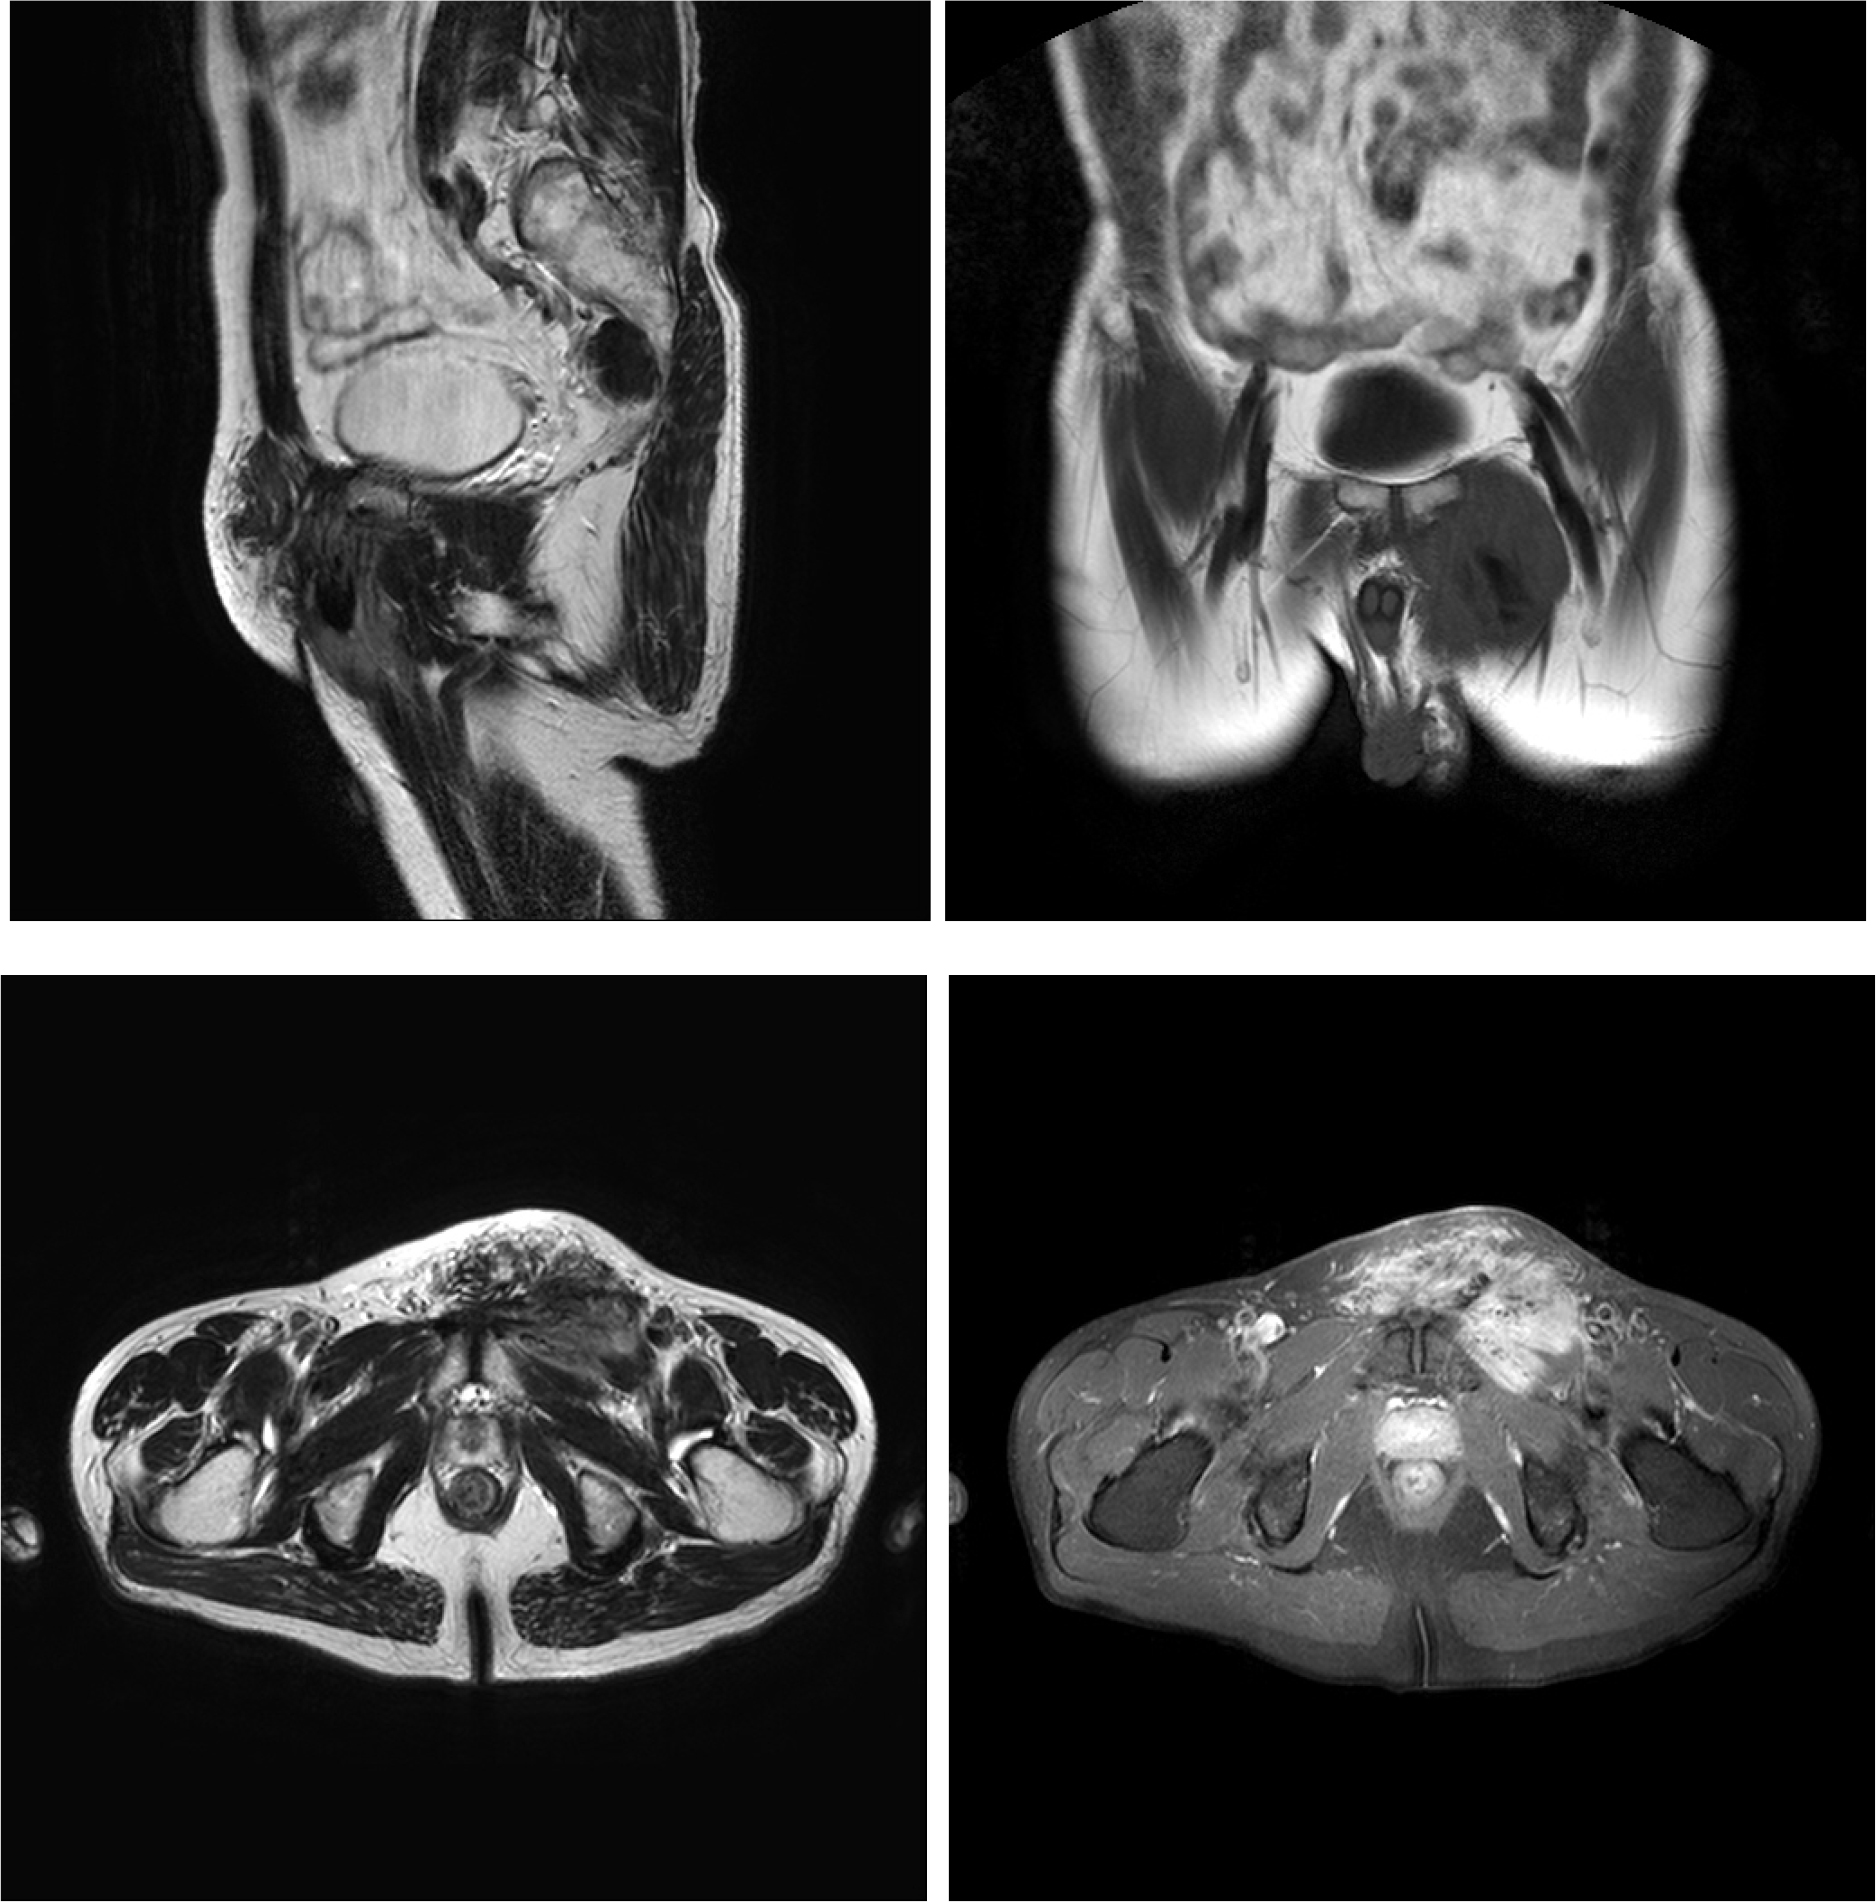

[그림 3] MRI에서 역시 좌측 서혜부에서 불규칙한 조영증강을 보이는 10 cm × 5 cm 크기의 연부 조직 종물이 관찰되었다. 방광이나 전립선, 주위 골반 뼈로의 직접 침윤 소견은 관찰되지 않았다.